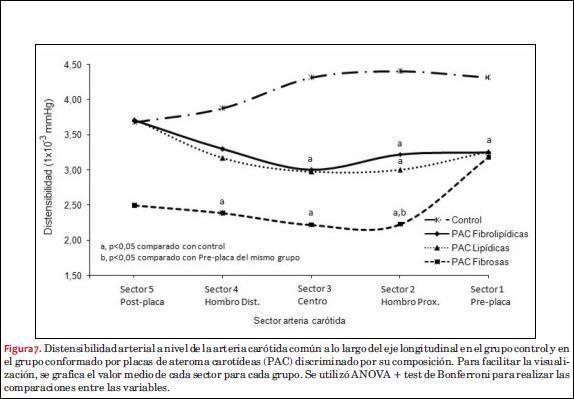

En la tabla 2 se presenta el valor medio y DE de la distensibilidad arterial para cada uno de los sectores estudiados en sujetos con PAC y arterias control, considerando cada una de ellas como una unidad de estudio independiente y separadas según su composición en los tres grupos mencionados. En la figura 7 se exponen dichos valores en forma gráfica para su mejor apreciación.

En forma general, los grupos de PAC estudiados mostraron diferencias en cuanto a la distensibilidad local a lo largo del eje longitudinal con respecto a las arterias controles (figura 7). La distensibilidad local de las arterias controles, por su parte, evidenció una tendencia global al descenso gradual (aumento de rigidez local) desde los sectores proximales a los distales. Todos los grupos de las arterias con PAC partieron de un punto de distensibilidad menor al grupo control en los sectores preplaca. No se evidenciaron diferencias estadísticamente significativas de distensibilidad entre los grupos con PAC en dicho sector. Las PAC con componente lipídico (FL y L) tendieron a presentar valores intermedios en el perfil de distensibilidad de los sectores 2-4 con respecto a las arterias control y grupo de placas FC.

El grupo de PAC FC evidenció el mayor grado de cambio de distensibilidad a nivel del hombro proximal. Empero, como se muestra en la figura 7, las placas con componente lipídico mostraron un comportamiento biomecánico homogéneo entre los sectores sucesivos estudiados, sin diferencias significativas y con una tendencia a aumentar su distensibilidad (“normalizarse”) en el sector posplaca. Las arterias con PAC FC mostraron aumento de la rigidez local a nivel del hombro distal y más allá de la placa en consideración.

Como se muestra en la figura 7, la disminución de la distensibilidad (aumento de rigidez) encontrada en el sector preplaca evidencia una alteración funcional en sectores arteriales sin afectación aterosclerótica macroscópica. Este hallazgo es consistente con el clásico concepto de que la aterosclerosis es una enfermedad arterial difusa, pero con manifestación segmentaria o focal(54,55), y, según nuestros resultados, parece independiente a la composición global de la PAC. Adicionalmente, la distensibilidad encontrada en las distintas PAC (independientemente de su ecogenicidad) fue menor en la mayoría de los sectores estudiados con respecto a las arterias carótidas controles. La disminución de la distensibilidad carotídea en sitios sin PAC se ha encontrado como un cambio precoz de la enfermedad aterosclerótica(34,36,39,56), por lo que dicho hallazgo podría representar fases tempranas de la enfermedad en sectores arteriales “normales”.

Las diferencias biomecánicas carotídeas más notorias fueron evidenciadas fundamentalmente en el sector del hombro proximal con respecto al sector arterial adyacente (figura 7, tabla 2). En concreto, nuestros resultados evidencian un cambio significativo de la distensibilidad del sector preplaca con respecto al hombro proximal en las PAC FC, con valores de rigidez arterial en el hombro proximal superiores a los encontrados en el sector preplaca. Contrariamente, las PAC con componente lipídico no presentaron dicho cambio, encontrando valores comparables en dichos sectores y corriente abajo.